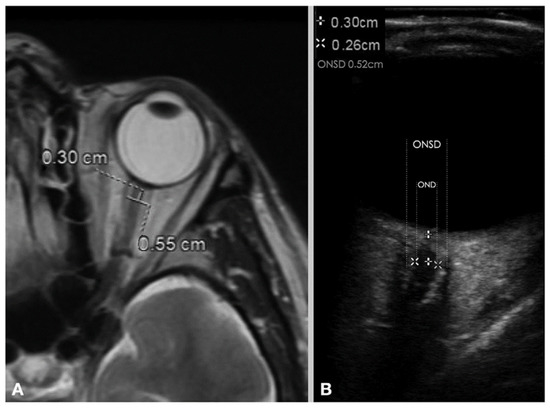

- Shokoohi, H.; Pyle, M.; Kuhl, E.; Loesche, M.A.; Goyal, A.; LeSaux, M.A.; Boniface, K.S.; Taheri, M.R. Optic Nerve Sheath Diameter Measured by Point-of-Care Ultrasound and MRI. J. Neuroimaging 2020, 30, 793–799. [Google Scholar] [CrossRef]

- Kimberly, H.H.; Noble, V.E. Using MRI of the optic nerve sheath to detect elevated intracranial pressure. Crit Care 2008, 12, 181. [Google Scholar] [CrossRef] [Green Version]

- Geeraerts, T.; Newcombe, V.F.; Coles, J.P.; Abate, M.G.; Perkes, I.E.; Hutchinson, P.J.; Outtrim, J.G.; Chatfield, D.A.; Menon, D.K. Use of T2-weighted magnetic resonance imaging of the optic nerve sheath to detect raised intracranial pressure. Crit Care 2008, 12, R114. [Google Scholar] [CrossRef] [Green Version]

- Kim, D.Y.; Kim, S.Y.; Hong, D.Y.; Sung, B.Y.; Lee, S.; Paik, J.H.; Jung, H.M. Comparison of ultrasonography and computed tomography for measuring optic nerve sheath diameter for the detection of elevated intracranial pressure. Clin. Neurol. Neurosurg. 2021, 204, 106609. [Google Scholar] [CrossRef] [PubMed]